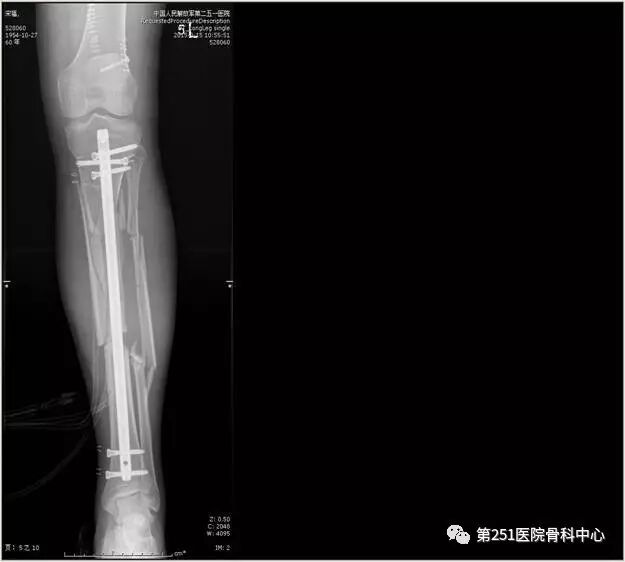

病例1:男性,40岁,车祸伤,胫腓骨多段骨折。

![]()